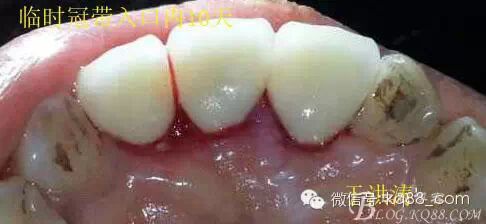

檢查:明顯可見22牙冠橫向斷裂至頸1/3處,近遠中與腭側斷裂至齦下??梢?/span>11牙冠斜向近中斷裂,近中與腭側均斷裂至齦下。21牙冠中1/3有裂痕。11 21 22松動(0),11 21叩(+),22叩(-),11 21 22探(-),11 21 22冷熱(-)。11 21 22唇側牙齦與粘膜和根尖相應部位未見明顯改變。11 22腭側牙齦增生性改變。11 21 22腭側粘膜和根尖相應部位未見改變。11 21 22舌側窩均有充填物。面部左右對稱無改變。余牙正常。(11,21,22牙冠顏色無改變)。 輔助檢查:X線片檢查11 22牙冠均有缺失。11 21 22 髓腔內均有充填物,11充填不到位, 21充填不實,22充填到位髓腔高密度影像。11 21 牙周膜有增寬,21根尖區(qū)有2mm左右低密度影像。未發(fā)現(xiàn)有牙根側穿或斷裂異物。 診斷:11,21慢性尖周炎,11,22殘冠。 治療計劃: 22無需治療。11 21 建議牙齒根管再治療。告知情況及費用。 1,11 21去除根充物。 2,11 21根管治療。 3,11 22纖維樁樹脂核修復。 4,高頻電刀去除11 22腭側牙齦組織到斷面。 5,11,21,22全瓷單冠修復牙齒。 治療過程:經(jīng)患者同意。H銼去除11 21原有充填物,未發(fā)現(xiàn)明顯滲出物,無異味。K銼疏通根管,VDW根測儀測量長度,11牙20mmWL,21牙20mmWL。S3鎳鈦器械預備根管。(全程1%次氯酸鈉沖洗EDTA溶解潤滑)試尖片顯示牙膠未到位,繼續(xù)向牙根尖各2mm進入預備。吸潮紙尖吸干根管,登士柏樹脂根充糊劑輸送至根尖部位,以測量數(shù)據(jù)用牙膠尖冷充側壓充填根管,3M玻璃離子封閉根管口。不可用患牙啃咬硬物,擇日冠修復。 輔助檢查:插針X線片顯示根管內充填物已經(jīng)取出。試尖片顯示牙膠尖未到位,繼續(xù)用K銼和機括向根尖預備。根充結束片顯示根充密實,無超充,無欠充。 醫(yī)囑:常規(guī)醫(yī)囑,不適隨診。 各步驟操作見下圖 于洪濤 2015.02.03 復 診 主訴:無疼痛,不適癥狀已經(jīng)消失。 檢查:11 21 充填物存在邊緣封閉完好,叩(-)松動(0)牙齦及周圍同初診。11 21 22無任何不適。 治療過程:由于患者自身原因即將兩個月來復診。拍X線片,去除11 22髓腔內部分牙膠,P鉆預備根管到達預定位置。粘結纖維樁,制作冠核。初預備11 21 22牙冠。高頻電刀按廠家要求功率和方法去除11 22腭側牙齦組織到達牙齒斷裂部位,調整檔位和功率繼續(xù)凝固和精修腭側組織,11 21 22排齦精修拋光。硅橡膠兩次法取模,可見模型完整肩臺清晰。制作臨時冠,科爾不含丁香油臨時冠粘結系統(tǒng)粘接。 模型送技師制作。預約義齒佩戴時間。(需術前牙齒比色) 輔助檢查:X線片顯示根尖低密度影像消失,牙周未見異常。X線片顯示纖維樁密合到位。 醫(yī)囑:不可用臨時牙肯咬硬物,不適隨診。 各步驟操作見下圖 于洪濤 2015.03.26 復 診 主訴:牙齒無癥狀,自感腭側術區(qū)舌舔粘膜不適。 檢查:臨時冠完整,無松動,邊緣緊密。牙齒無疼痛,唇側牙齦無明顯紅腫,腭側牙齦愈合良好,牙冠肩臺邊緣清晰。腭側牙齦術區(qū)中度觸及有少量滲血。 治療過程:義齒制作完成。去除臨時冠及粘結物。義齒試戴調整完全就位,無懸突,無縫隙。清洗義齒,氫氟酸處理義齒50秒(加強醫(yī)患防護),沖洗吹干,偶聯(lián)劑處理備用。基牙37%酸處理15秒,沖洗吹干,隔濕,排齦,涂第五代粘結劑。小蜜蜂雙固化樹脂水門汀激活攪拌注入義齒中,按順序就位,加壓力,牙線去除牙縫隙多余樹脂,涂阻氧劑,基牙唇腭側各光照固化3秒之后去除多余水門汀取出排齦線,繼續(xù)光照固化牙齒每個面20秒。精細查找去除多余水門汀。 醫(yī)囑:1,患牙咀嚼硬物加以注意。 2,常規(guī)醫(yī)囑,不適隨診,。 3,加強口腔衛(wèi)生意識。定期復診檢查。 各步驟操作見下圖 于洪濤 2015.04.07 回訪病例 主訴:咀嚼食物非常自如,無任何不適。 檢查:義齒牙體完整。無松動,無叩痛。唇側牙齦紅潤質韌無萎縮,腭側術區(qū)牙齦愈合良好,無炎癥改變。唇腭側根尖相應部組織無改變。余牙正常。 輔助檢查:X線片顯示牙根及周圍未見異常。未見骨萎縮。牙冠及頸部未見異常。 醫(yī)囑:定期檢查義齒,不適隨診。 各步驟操作見下圖 于洪濤2015.04.28